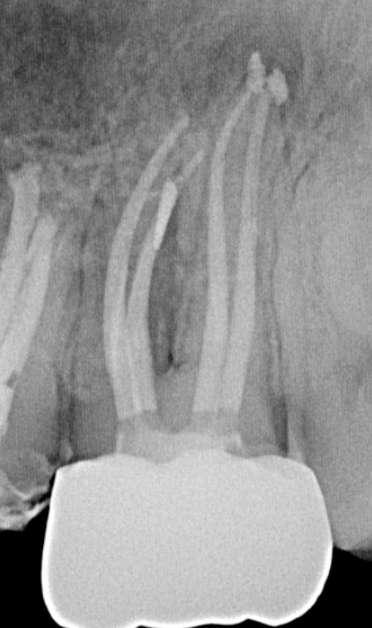

Wenn man sich dieses präoperative Röntgenbild ansieht, sind zwei Hinweise zu diesem endodontischen Fall zu erkennen (Abb. 1): Obliteration der Pulpakammer und enge Kanäle Ungewöhnliche Anatomie der distalen Wurzel

FALLBERICHT: Abb.1 Abb.2

Die abschließende Spülung erfolgte zunächst eine Minute mit schallaktivierter EDTA-Lösung, gefolgt von einer Minute mit schallaktivierter NaOCl-Lösung. Das Wurzelkanalsystem wurde gespült, getrocknet und dann mit einer hydraulischen Single-Cone-Technik und einem biokeramischen Sealer (BUSA, BC Sealer) verschlossen. Zur Überprüfung der Behandlungsqualität wurden zwei periapikale Röntgenaufnahmen aus verschiedenen Winkeln angefertigt (Abb. 3-4).

Der Verdacht des Klinikers auf eine ungewöhnliche Anatomie der distalen Wurzel wurde durch das abgewinkelte Röntgenbild bestätigt, das eine abrupte versteckte Krümmung im apikalen Drittel des Kanals zeigte. Trotzdem ermöglichte der Crown-Down-Ansatz (zunächst Aufbereitung des koronalen und mittleren Teils, wodurch koronale Interferenzen reduziert werden) und die richtige Auswahl sehr flexibler und widerstandsfähiger

Abb.3 Abb.4